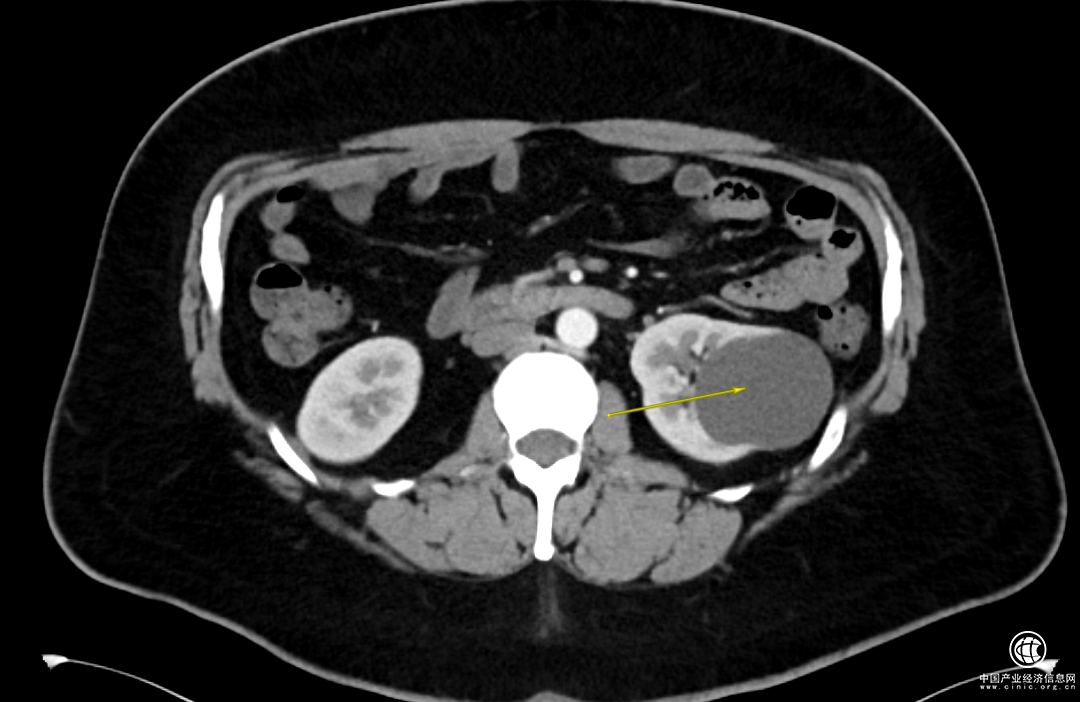

1個月前,Adam感覺到左側(cè)腰背部偶爾會有陣發(fā)性脹痛不適的情況,于是做了泌尿系彩超,發(fā)現(xiàn)左腎的囊腫已經(jīng)超過6cm了。

腎囊腫是指腎臟內(nèi)出現(xiàn)的大小不等、與外界不通的囊性腫塊,一般沒啥子癥狀,也不需要特殊治療!

但是當(dāng)囊腫超過4cm,就要做相應(yīng)治療了。

經(jīng)過一系列的檢查,詹紹洋主任診斷Adam是單純性腎囊腫,安排住院。

詹紹洋主任決定在全麻下行腹腔鏡下左腎囊腫去頂術(shù),將腎囊腫囊壁進(jìn)行切除,切除這部分囊壁后原先腎囊腫的完整性就被破壞,它的張力也就隨之消失,切除囊壁的腎臟部位就基本不會再次積聚囊液產(chǎn)生壓力從而再次形成囊腫。

小于4cm的單純囊腫,每半年至一年復(fù)查超聲或者CT即可;

大于4cm,或者有腰背部疼痛不適,或者囊腫壓迫影響腎功能時候需要手術(shù)處理;

CT或B超顯示有多房、有分隔、鈣化、有實性成分等復(fù)雜囊腫,需進(jìn)一步就診。